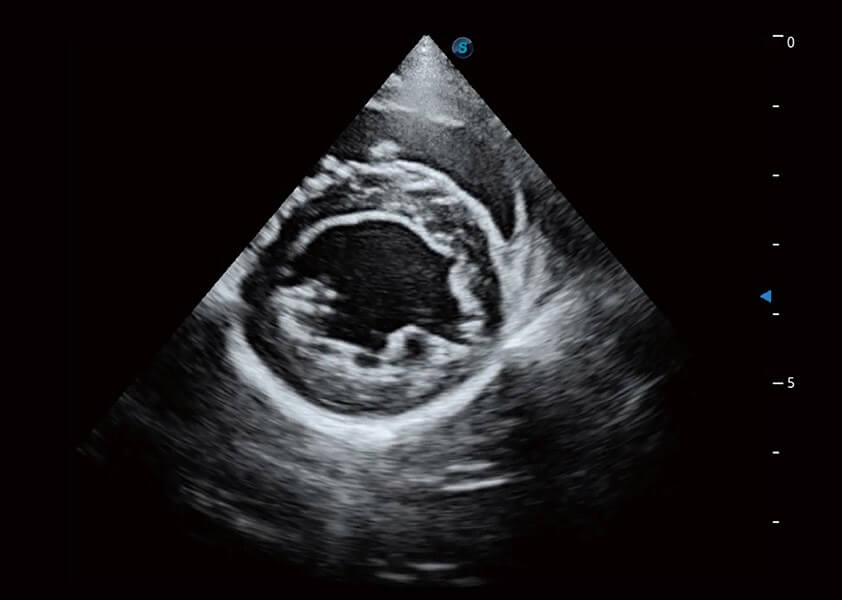

ProPet 60 作为一款高端台式动物超声设备,为动物医生的日常诊断提供了一系列贴合动物临床需求、解决临床实际问题的高级成像功能。凭借全系列高清探头,满足医生对腹部、心脏、生殖、浅表、肌骨等成像的所有需求,切实帮助您提升检查效率,提高诊断信心。

兽用彩色多普勒超声诊断系统

动物是人类最亲密的朋友和最值得信赖的伙伴。银河集团官网也一直致力于探索动物专用的超声影像解决方案。 全新推出的ProPet系列,是银河集团官网在动物超声影像智能化、专业化、精准化的一次跨越式革新。动物不能用言语来表述自己的不适,通过超声影像,ProPet系列搭建了动物医生与不同物种沟通的“桥梁”,为动物医生注入了“治愈之力”。